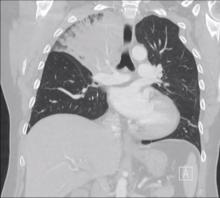

A 52-year-old female smoker presented to the ER with pneumonia. Her chest x-ray showed consolidation of the right upper lobe (RUL). Flexible bronchoscopy revealed that the orifice of the right upper bronchus was fully occluded by a tumor mass, and biopsy confirmed a typical carcinoid tumor. Her chest CT scan showed the right upper lobe fully consolidated and a tumor obstructing the RUL orifice, without evidence of hilar or mediastinal adenopathy. The patient was treated with antibiotics for 15 days, and was readmitted for surgical treatment.